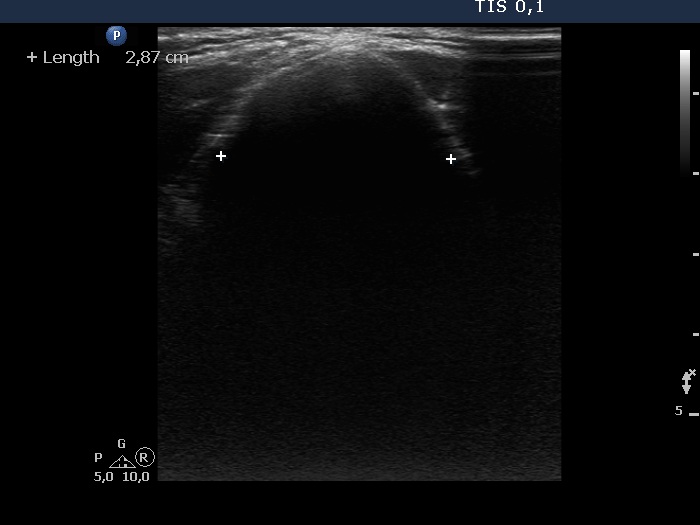

Clinical presentation: A 41-year-old man was referred for aspiration cytology. First, he was examined for nodular goiter 9 years ago when FNA resulted in benign colloid goiter from a nodule with a 21-mm maximal diameter. Recently, cytology was repeated because the nodule has been grown to 42 mm. This time FNA was non-diagnostic.

Ultrasonography. The thyroid was echonormal. There was a hypoechoic nodule in the right lobe. The dimensions of the nodule were 39x21x42 mm, width, depth and length, respectively. The lesion had a partial halo and both perinodular and intranodular vascularity.